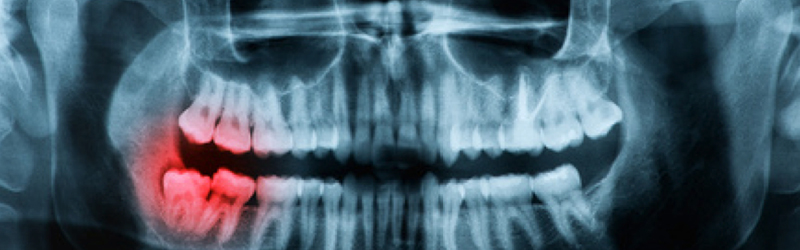

Whenever you go to the dentist for a checkup, dental X-rays are an essential component of the usual examination. In the event that there is anything wrong with your teeth, these x-rays will assist your dentist in determining the next step to take towards correcting the issue. To verify that there are no cavities, fractured teeth, or other issues with your teeth, it is always a good idea to have x-rays taken of them.